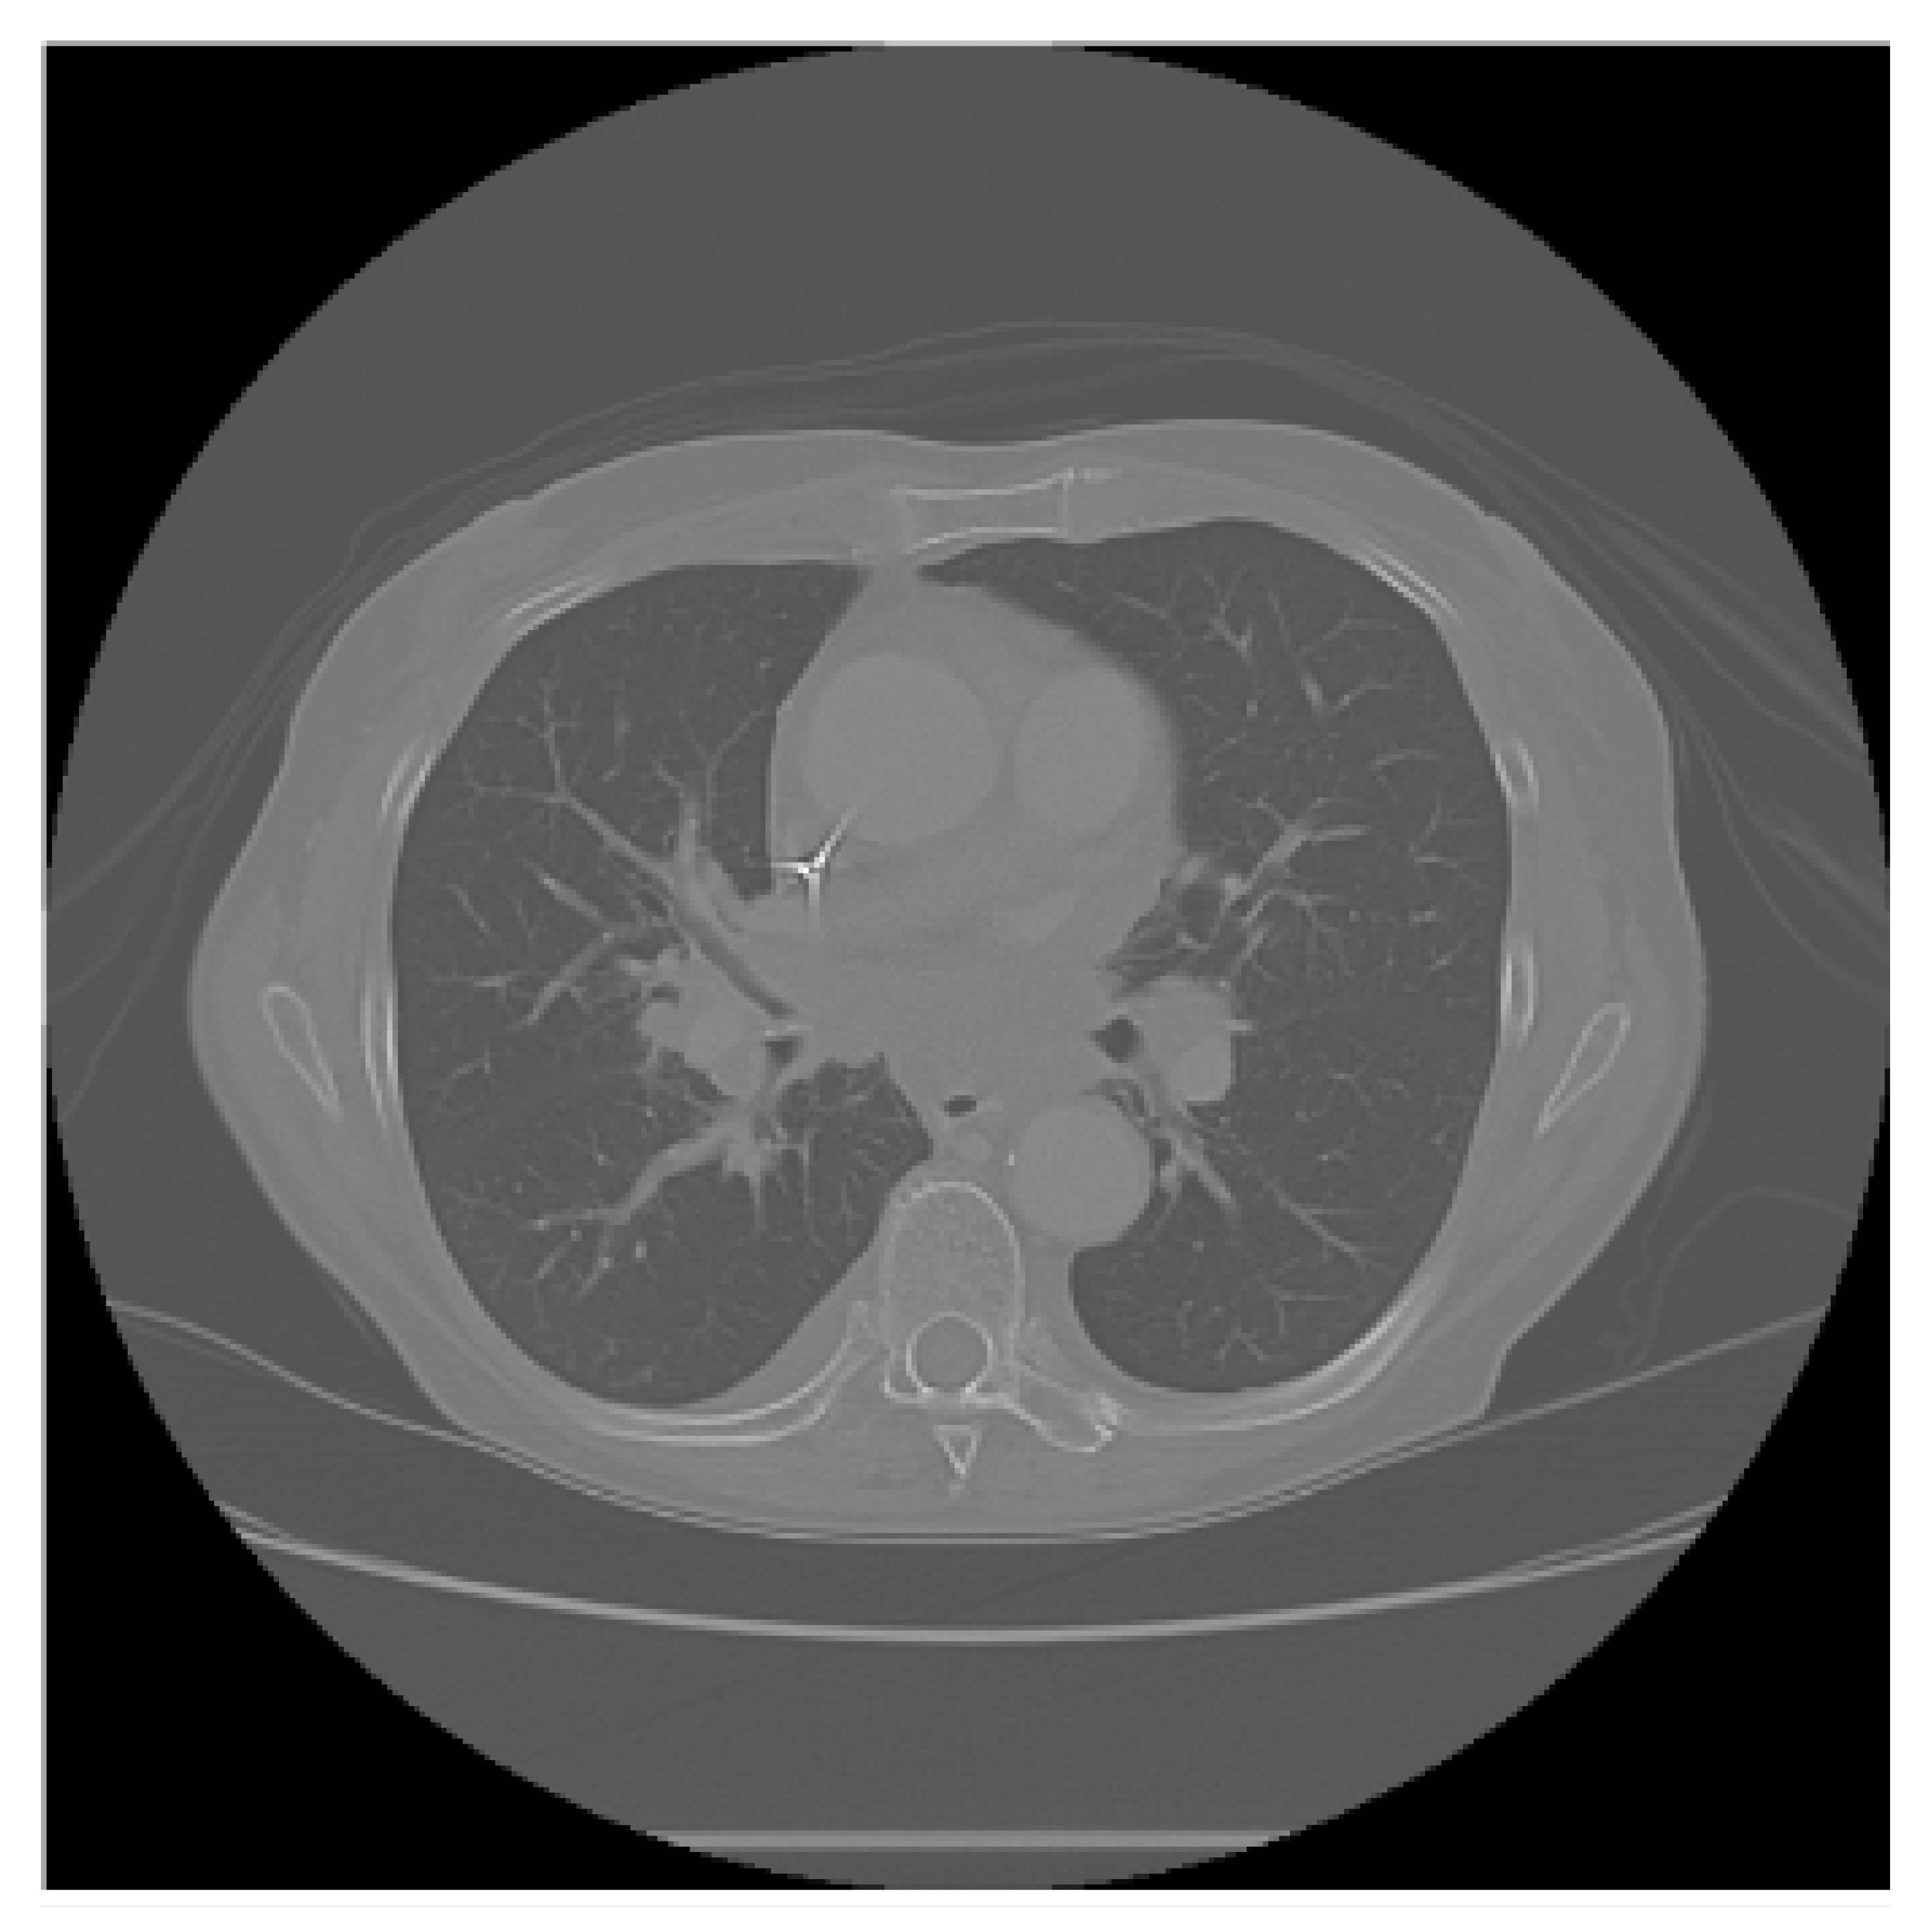

The APILungCancer interface provides intuitive functionality for loading and analyzing DICOM medical images. In the Load DICOM Images section, users can select and process CT scans for lung cancer evaluation. Once an image is loaded and analysis is performed, the software presents a visualization of the image along with the predicted probability of cancer (Table 7). Our study focused on lung cancer, including subtypes such as adenocarcinoma, squamous cell carcinoma, and small cell carcinoma. About 1000 training images and 300 test images from the CMB-LCA dataset were used to develop and validate the system.

In this example (Figure 5), the DICOM image 1-27.dcm from the test set was processed and the software calculated a cancer probability of 0.4267 (42.67%), indicating a high likelihood of malignancy.

Figure 5.

Determination of the probability of lung cancer. Example output of the system for the image 1-27.dcm, yielding a predicted probability of 42.67%, consistent with Table 7.

This value matches the result in Table 7, confirming the consistency of the predictions generated by the AI-based model integrated into the system.